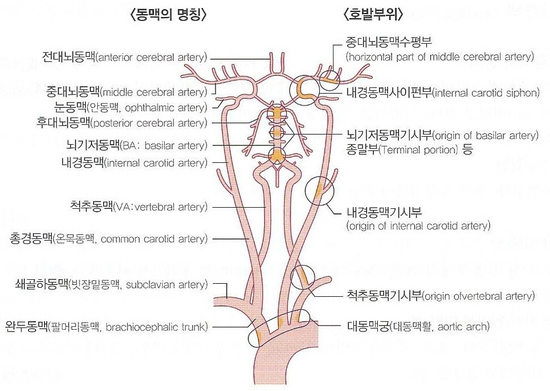

혈전의 호발 부위의 신경 증상은 뇌경색 부위와 크기, 그리고 측부 순환 혈액량에 따라 결정됩니다. 혈전이 생기는 호발 부위는 위 그림과 같고 비교적 굵은 뇌동맥이 폐쇄되었을 때의 증상은 아래 표와 같습니다.전대뇌동맥폐쇄치매, 인격변화, 자발성결핍, 이상반사중대뇌동맥폐쇄의식장애, 반신마비, 지각장애, 언어장애후대뇌동맥폐쇄시야장애, 시각인지불능, anton실명